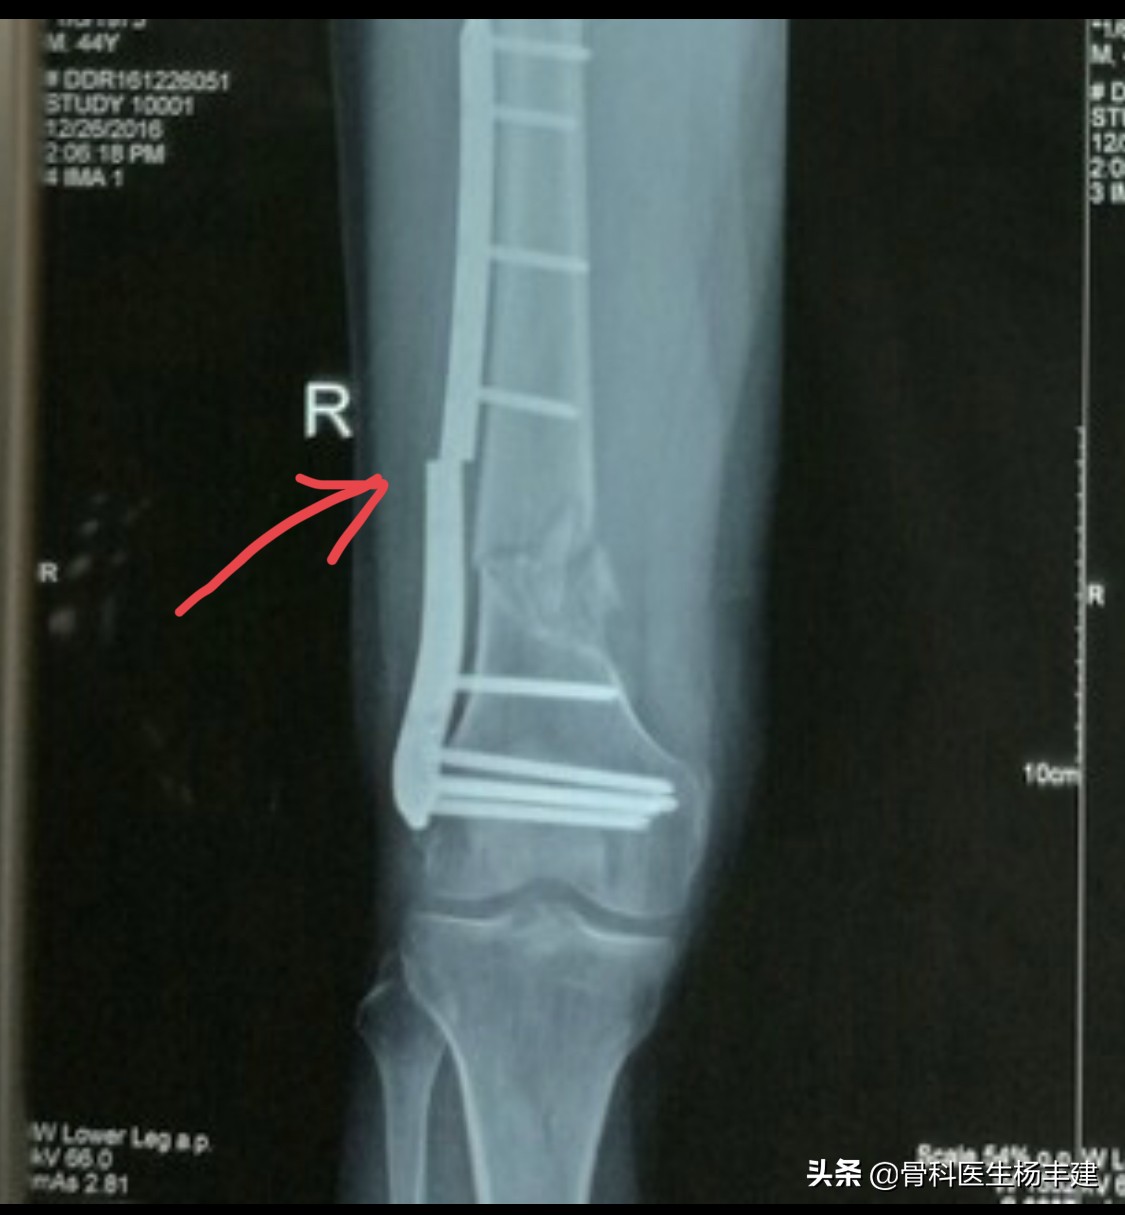

大腿骨固定后9个月,出现钢板断裂的病例

骨折断端萎缩,间隙增大,典型的“骨折不愈合”表现